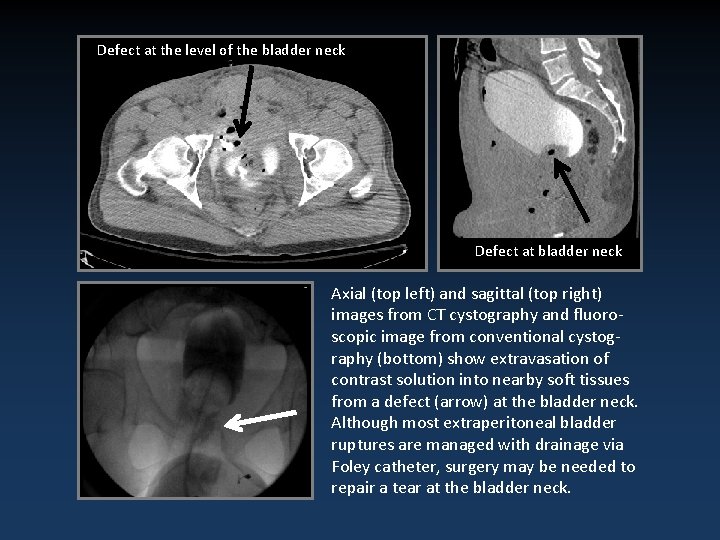

Defect at the level of the bladder neck Defect at bladder neck Axial (top left) and sagittal (top right) images from CT cystography and fluoroscopic image from conventional cystography (bottom) show extravasation of contrast solution into nearby soft tissues from a defect (arrow) at the bladder neck. Although most extraperitoneal bladder ruptures are managed with drainage via Foley catheter, surgery may be needed to repair a tear at the bladder neck.